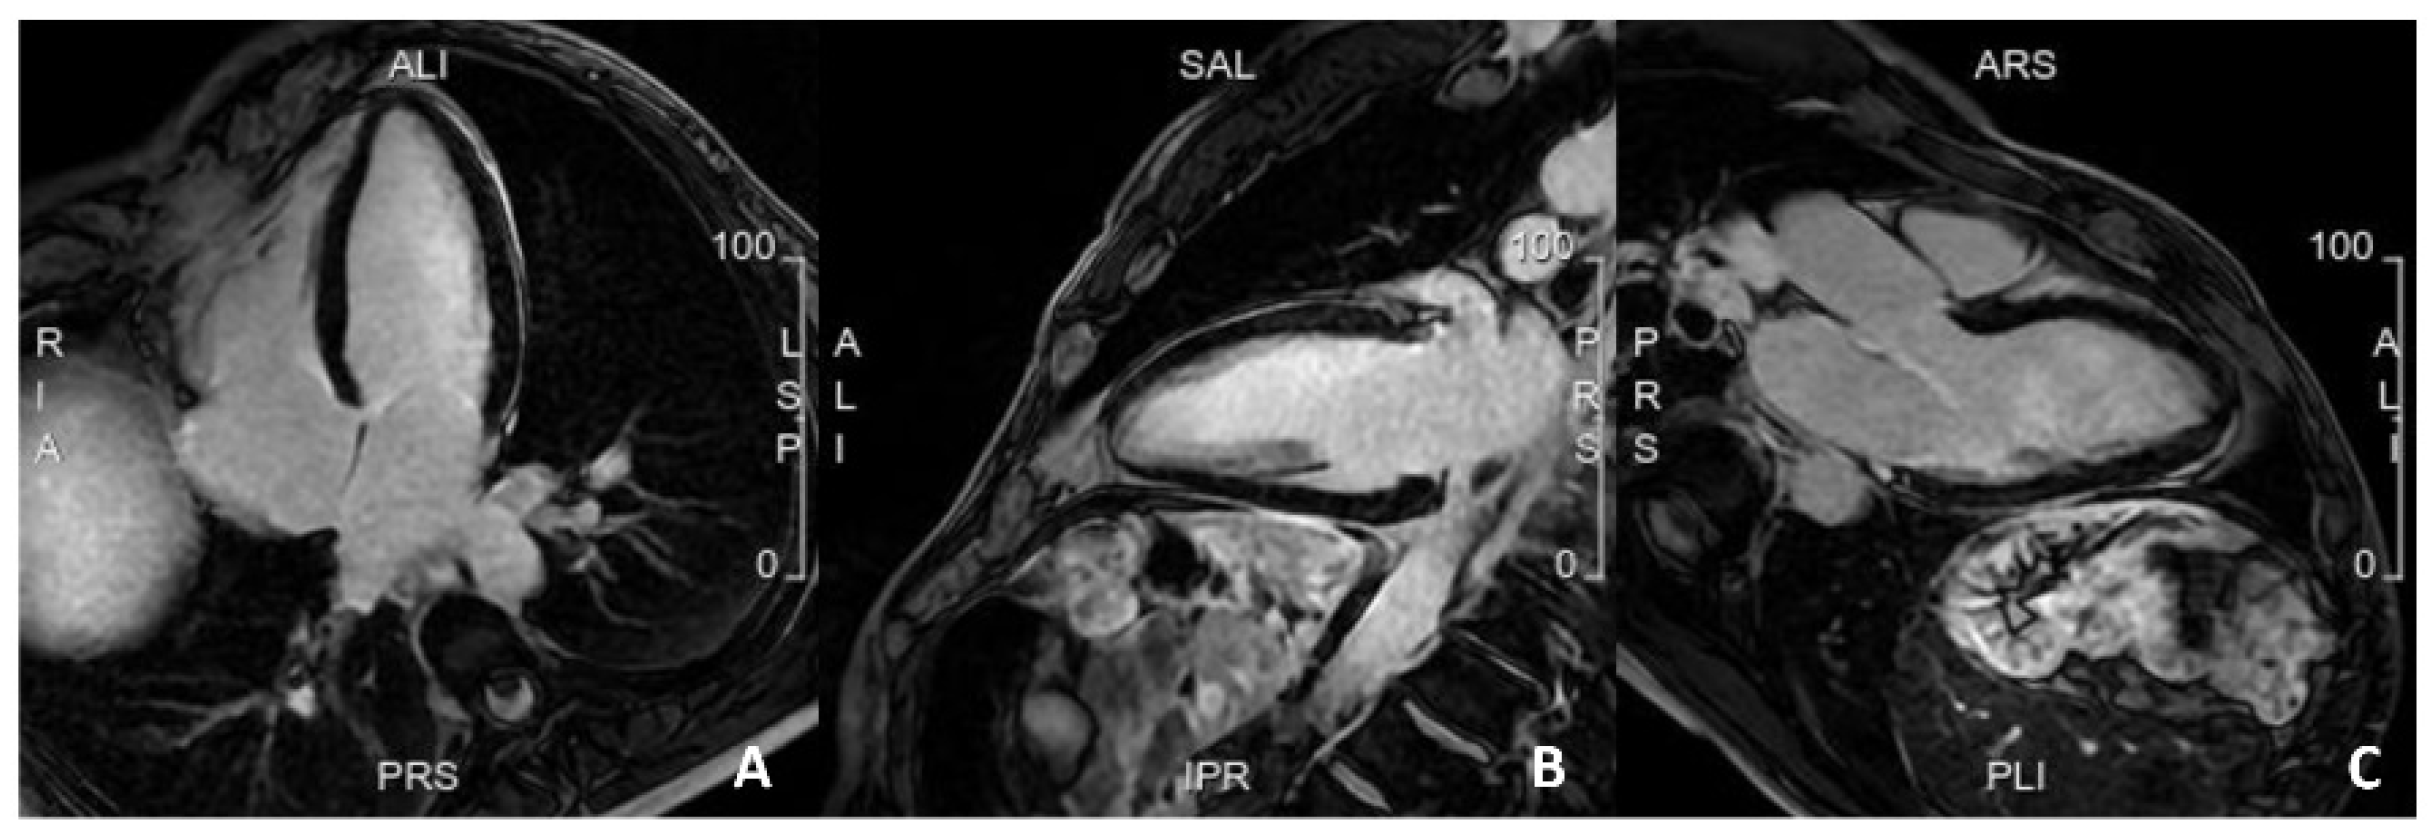

Figure 2.

A case of a patient with a family history of sudden cardiac death, with frequent but isolated ectopic ventricular beats. Cardiac MRI was completely normal, with no evidence of myocardial fibrosis. (A). 4 Chamber view; (B). 2 Chamber view; (C). 3 Chamber view.